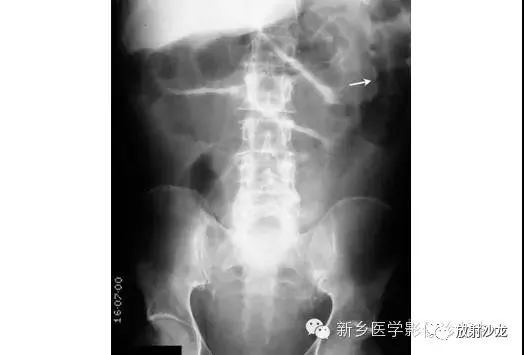

上图为一58岁男性,因1周前非特异性消化不良,行上消化道钡餐检查,做的腹部平片。患者最初表现为不确切的腹部不适和便血。现在又出现了腹痛和腹膜炎。箭头所指的典型表现是什么,诊断是什么?

箭头指向缺血穿孔性肠病患者的浅浮雕征。这也被称为双壁征或Rigler征。通常仅一侧肠壁可以看到。当双侧都能看到时,它表示腔内和腔外都有气体。当病人腹痛症状逐渐加重,肠壁穿孔是很有可能的。该患者手术过程中发现肠道脾曲缺血穿孔性肠病。